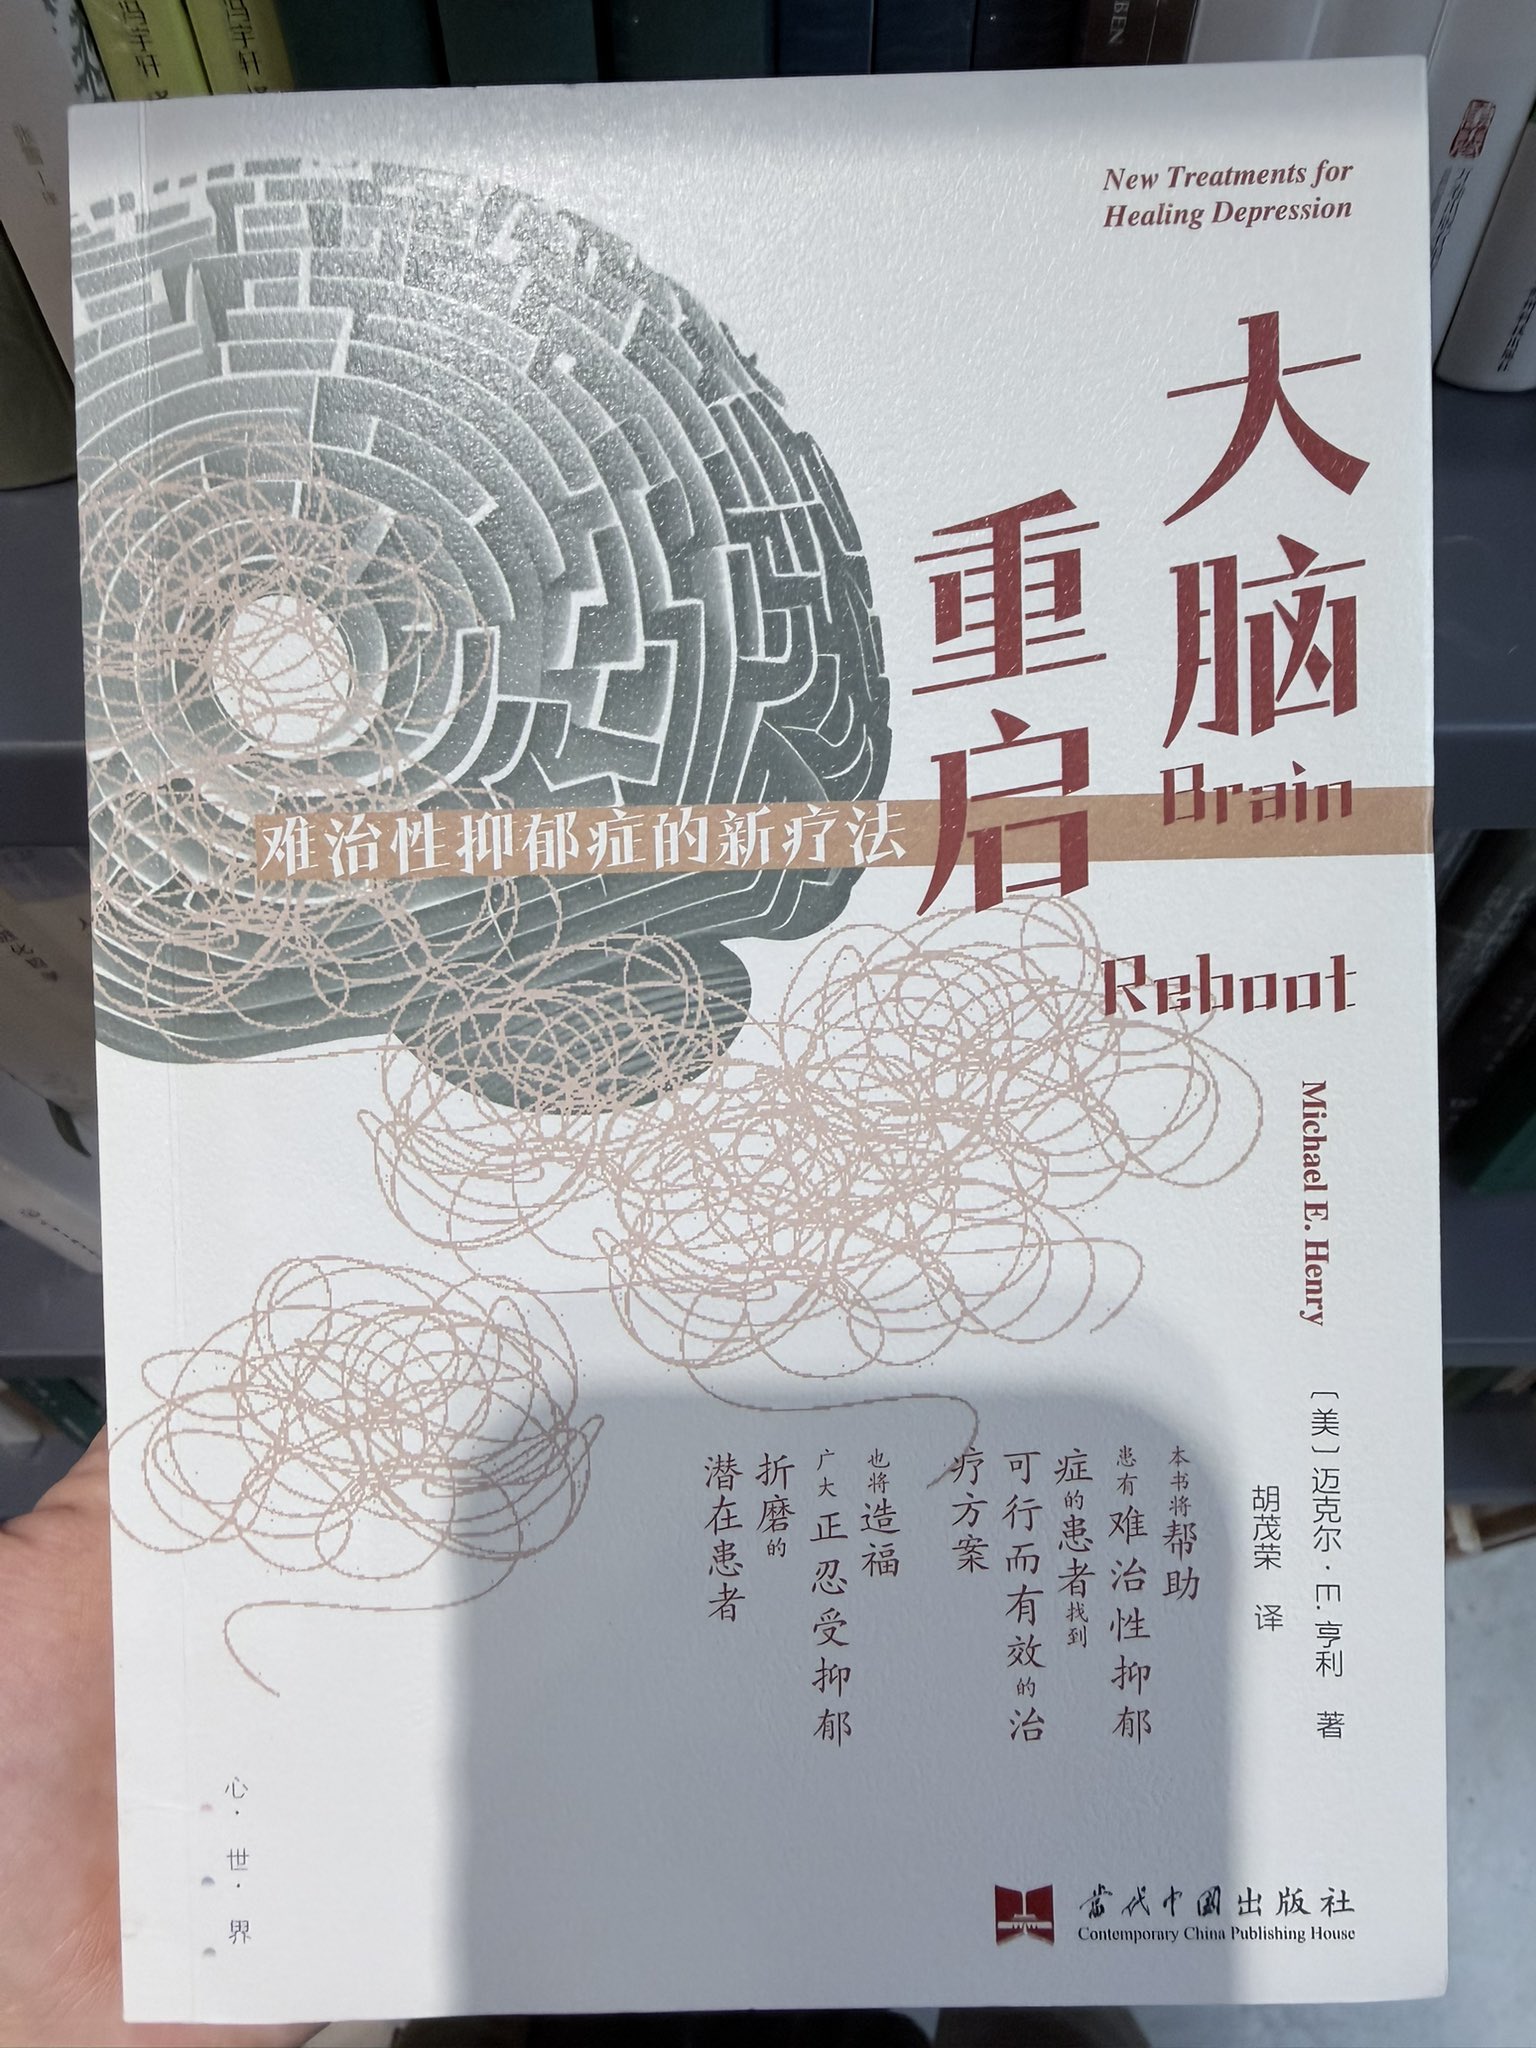

真的会推荐发作的时候或难治性抑郁做氯胺酮🥺关于价格,不算私立医院或住院的情况,一般一次是800...其实以前药费也有吃到过很高

不会像mect那样副作用很可怕,我的感觉是几乎没有负面影响

顺着这个思路用的auv对我效果也很好。那么漫长的寻找和尝试总算有了相对稳定的解法..太好了

炽烈已极 @AnIncandescence菜单(不是)

这本书挺好的,抗抑郁新疗法基本都提了,我大多都试过x

写了传统疗法,氯胺酮,经颅磁,电休克,运动睡眠营养,auv致幻剂mdma https://t.co/xTfmtUfIIk[图片媒体不可用]